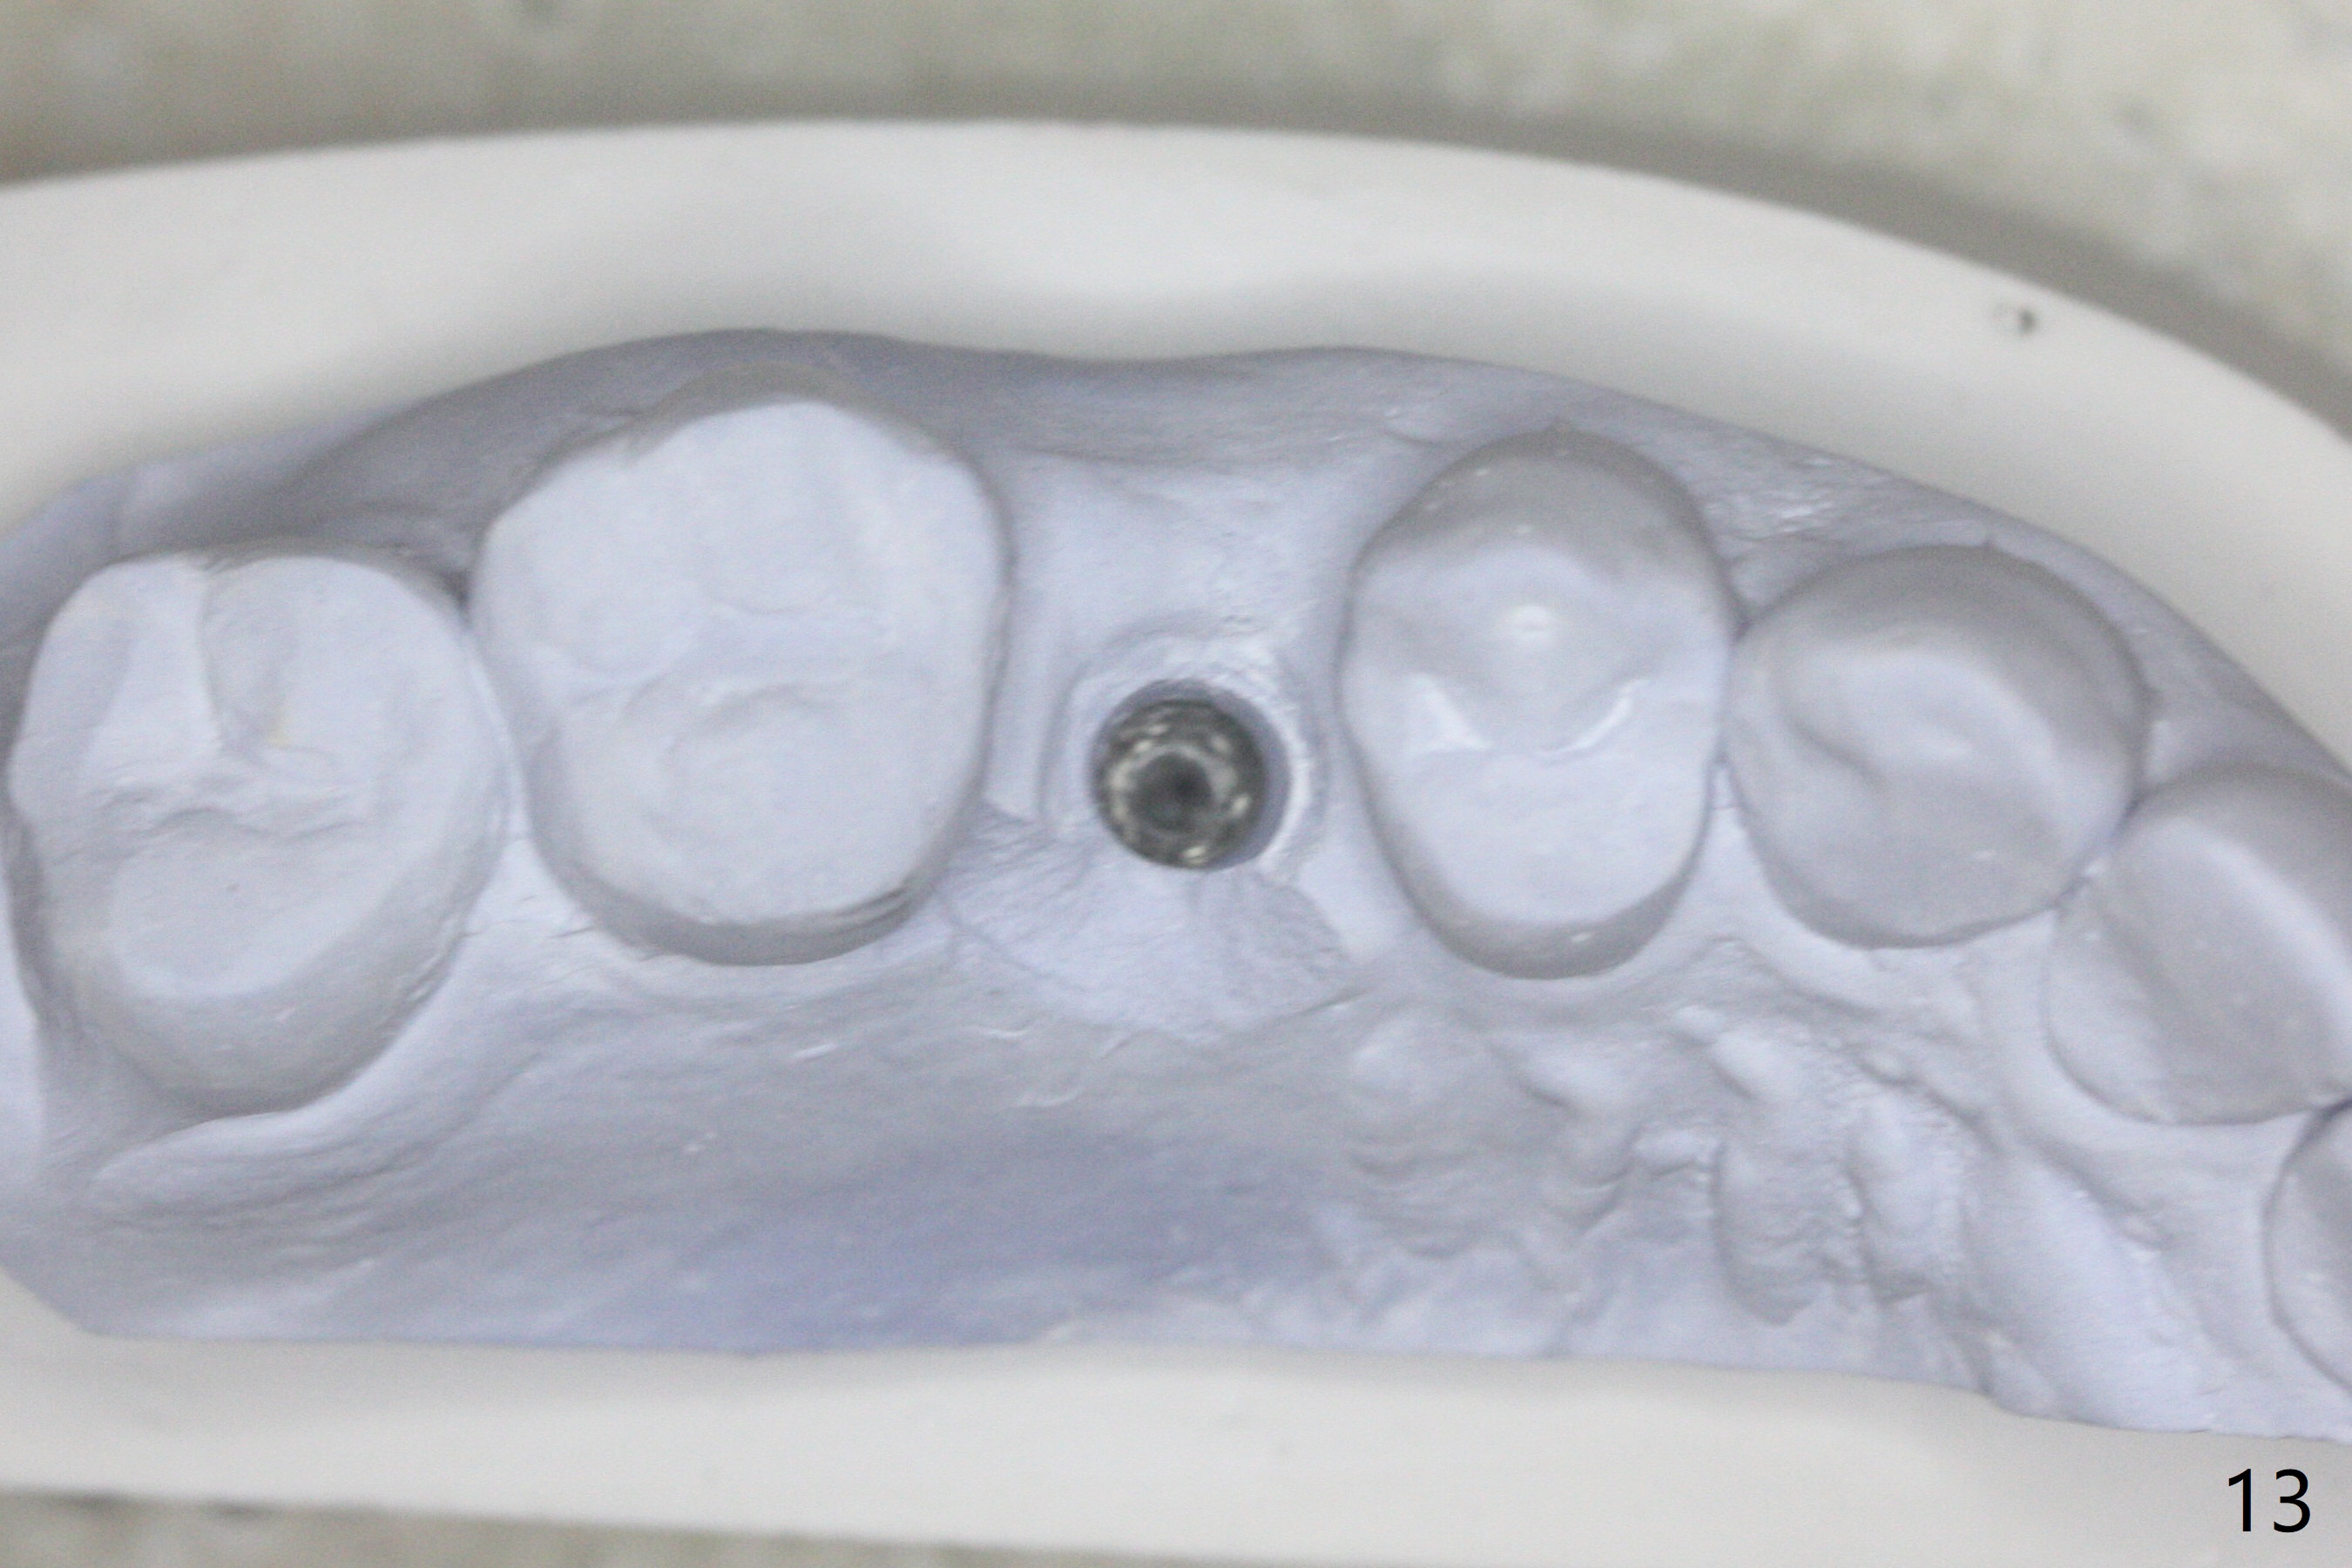

40岁女右上5近中龈下龋齿(图一),要求拔除植牙,上颌窦底板已经破坏穿孔,但是窦膜完整(图二)。清创后,放置PRF膜和粘性骨粉,用挖匙和上颌窦充填器尽量往上面推。然后放置导板,使用2.2x7.3 和3.0x7.3毫米钻头完成钻洞,可能无意中把骨粉推入上颌窦,之后利用报废植体(图三,四)完成提升,同时修补根尖缺损(利用之前放置的骨粉,图四:*,与图五(术前)对比)。当报废植体取出时,植牙窝已经形成,再放入少量骨粉,植入同样大小(之前扭力高)正式植体(不同品牌,图六,七),这时扭力低,放置愈合帽和骨粉(图七,八),以及6-9个月吸收膜,使用牙周胶水固定(图九),最后牙周敷料。术中术后几个小时没有上颌窦膜破裂迹象。术后一周牙周敷料松动,造成不适,去除时,膜好像粘附于敷料一起去除,骨粉暴露(图十),使用树脂敷料固定。后者术后一个月去除,因为局部有臭味。术后4个月切开放置愈合基台(图十一),术后五个月放置修复基台(图十二),使用塑料袖取模。术后5.5月同时放置牙冠和基台,十分顺手,口内粘固,之后同时取出,除去多余粘固剂,然后拧紧30Ncm(厂家推荐35 Ncm),一切非常顺利,觉得拍摄X光片是多余的。美中不足的是开孔(access hole)偏腭侧(图十二;由于自由手植入植体,与设计对比)。